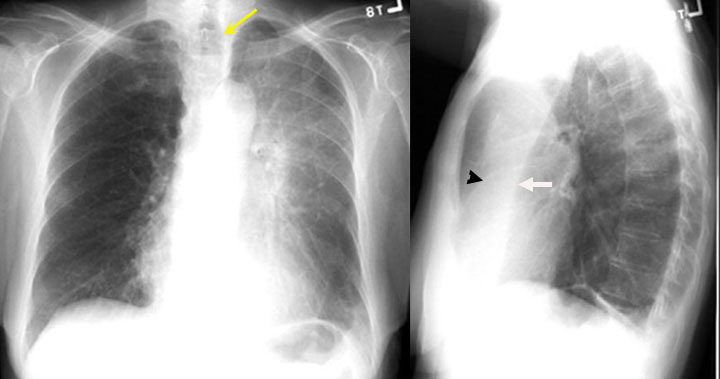

Dr Pepe S Diploma Casebook Case 115 Solved Blog

Lateral Chest X Ray Demonstrated Increase In Retrosternal And Download Scientific Diagram